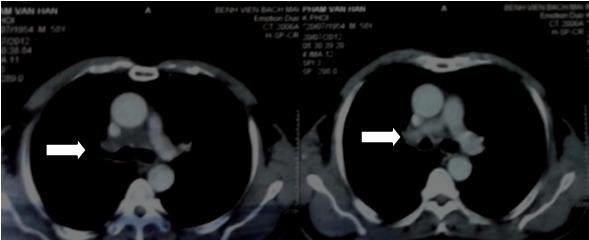

Hình 1: Chụp cắt lớp lồng ngực: có khối  u vùng trung thất, bao quanh khí quản và phế quản gốc